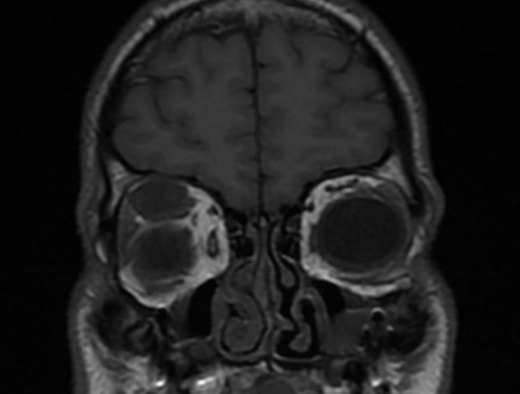

Imaging of localized neurofibromas shows smoothly marginated ovoid lesions[1][12] which may or may not be lobulated. On CT, they appear isodense or hypodense to extraocular muscles and show variable contrast enhancement with some reports of ring-enhancing characteristics.[1][10] MRI demonstrates low-moderate T1 signal intensity and moderate-high T2 signal intensity. There may be heterogeneity of signal strength within the lesion, reflecting the mixed histopathology and vascularity of the tumors.[1][12] As with CT, contrast enhancement is variable on MRI.

T1 MRI image showing a 24x12x16 millimeter right, superior orbital neurofibroma that appears as an isointense, well circumscribed, extraconal mass.

Imaging of plexiform neurofibromas demonstrates multi-lobulated, non-encapsulated tumors that lack clear margination[1][15] and cause diffuse thickening of the involved nerve. As with localized neurofibromas, they tend to show low attenuation on CT, isointensity on T1, and hyperintensity on T2 weighted images[15] with variable contrast enhancement.